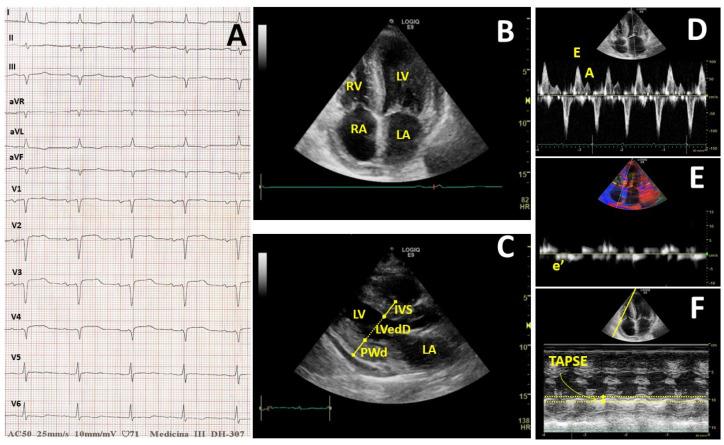

Amyloidosis is due to deposition of an excessive amount of protein in many parenchymal tissues, including myocardium. The onset of cardiac Amyloidosis (CA) is an inauspicious prognostic factor, which can lead to sudden death. We retrospectively analyzed 135 patients with systemic amyloidosis, admitted to our ward between 1981 and 2019. Among them, 54 patients (46.30% F/53.70% M, aged 63.95 ± 12.82) presented CA at baseline. In 53 patients, it was associated with a multiorgan involvement, while in one there was a primary myocardial deposition. As a control group, we enrolled 81 patients (49.30% F/50.70% M, aged 58.33 ± 15.65) who did not meet the criteria for CA. In 44/54 of patients CA was associated with AL, 5/54 with AA and 3/54 of patients with ATTR, and in 1/54 AL was related to hemodialysis and in 1/54 to Gel-Amyloidosis. The most common AL type was IgG (28/44); less frequent forms were either IgA (7/44) or IgD (2/44), while seven patients had a λ free light chain form. The 32 AL with complete Ig were 31 λ-chain and just one k-chain. CA patients presented normal BP (SBP 118.0 ± 8.4 mmHg; DBP 73.8 ± 4.9 mmHg), while those with nCA had an increased proteinuria ( = 0.02). TnI and NT-proBNP were significantly increased compared to nCA ( = 0.031 and = 0.047, respectively). In CA patients we found an increased LDH compared to nCA ( = 0.0011). CA patients were also found to have an increased interventricular septum thickness compared to nCA ( = 0.002), a decreased Ejection Fraction % ( = 0.0018) and Doppler velocity E/e' ratio ( = 0.0095). Moreover, CA patients had an enhanced right atrium area ( = 0.0179), right ventricle basal diameter ( = 0.0112) and wall thickness ( = 0.0471) compared to nCA, and an increased inferior cava vein diameter ( = 0.0495) as well. TAPSE was the method chosen to evaluate systolic function of the right heart. In CA subjects very poor TAPSE levels were found compared to nCA patients ( = 0.0495). Additionally, we found a significant positive correlation between TAPSE and lymphocyte count (r = 0.47; = 0.031) as well as Gamma globulins (r = 0.43, = 0.033), Monoclonal components (r = 0.72; = 0.047) and IgG values (r = 0.62, = 0.018). Conversely, a significant negative correlation with LDH (r = -0.57, = 0.005), IVS (r = -0.51, = 0.008) and diastolic function evaluated as E/e' (r = -0.60, = 0.003) were verified. CA patients had very poor survival rates compared to controls (30 vs. 66 months in CA vs. nCA, respectively, = 0.15). Mean survival of CA individuals was worse also when stratified according to NT-proBNP levels, using 2500 pg/mL as class boundary (174 vs. 5.5 months, for patients with lower vs. higher values than the median, respectively = 0.013). In much the same way, a decreased right heart systolic function was correlated with a worse prognosis (18.0 months median survival, not reached in subjects with lower values than 18 mm, = 0.0186). Finally, our data highlight the potential prognostic and predictive value of right heart alterations characterizing amyloidosis, as a novel clinical parameter correlated to increased LDH and immunoglobulins levels. Overall, we confirm the clinical relevance of cardiac involvement suggests that right heart evaluation may be considered as a new marker for clinical risk stratification in patients with amyloidosis.

淀粉样变性是由于大量蛋白质沉积于包括心肌在内的许多实质组织中所致。心脏淀粉样变性(CA)的发生是一个不良的预后因素,可导致猝死。我们回顾性分析了1981年至2019年间入住我们病房的135例系统性淀粉样变性患者。其中,54例患者(女性占46.30%/男性占53.70%,年龄63.95±12.82岁)基线时存在CA。53例患者中,CA与多器官受累相关,而1例为原发性心肌沉积。作为对照组,我们纳入了81例不符合CA标准的患者(女性占49.30%/男性占50.70%,年龄58.33±15.65岁)。54例患者中,44例CA与AL相关,5例与AA相关,3例与ATTR相关,1例AL与血液透析相关,1例与凝胶淀粉样变性相关。最常见的AL类型是IgG(44例中的28例);较不常见的类型是IgA(44例中的7例)或IgD(44例中的2例),7例患者为λ游离轻链形式。32例具有完整Ig的AL患者中,31例为λ链,仅1例为κ链。CA患者血压正常(收缩压118.0±8.4 mmHg;舒张压73.8±4.9 mmHg),而无CA患者蛋白尿增加(P = 0.02)。与无CA患者相比,CA患者的肌钙蛋白I和N末端脑钠肽前体显著升高(分别为P = 0.031和P = 0.047)。与无CA患者相比,我们发现CA患者的乳酸脱氢酶升高(P = 0.0011)。与无CA患者相比,CA患者的室间隔厚度也增加(P = 0.002),射血分数百分比降低(P = 0.0018),多普勒速度E/e'比值降低(P = 0.0095)。此外,与无CA患者相比,CA患者的右心房面积增大(P = 0.0179)、右心室基底直径增大(P = 0.0112)和壁厚增加(P = 0.0471),下腔静脉直径也增加(P = 0.0495)。采用三尖瓣环平面收缩期位移(TAPSE)评估右心收缩功能。与无CA患者相比,CA患者的TAPSE水平非常低(P = 0.0495)。此外,我们发现TAPSE与淋巴细胞计数(r = 0.47;P = 0.031)、γ球蛋白(r = ;0.43,P = 0.033)、单克隆成分(r = 0.72;P = 0.04)和IgG值(r = 0.62,P = 0.018)之间存在显著正相关。相反,与乳酸脱氢酶(r = -0.57,P = 0.005)、室间隔(r = -0.51,P = 0.008)和以E/e'评估的舒张功能(r = -0.60,P = 0.003)之间存在显著负相关。与对照组相比,CA患者的生存率非常低(CA组与无CA组分别为30个月和66个月,P = 0.15)。当以2500 pg/mL作为界值根据N末端脑钠肽前体水平分层时,CA患者的平均生存期也较差(低于中位数与高于中位数的患者分别为174个月和5.5个月,P = 0.013)。同样,右心收缩功能降低与较差的预后相关(中位生存期18.0个月,三尖瓣环平面收缩期位移低于18 mm的患者未达到,P = 0.0186)。最后,我们的数据强调了淀粉样变性特征性右心改变作为与乳酸脱氢酶和免疫球蛋白水平升高相关的新临床参数的潜在预后和预测价值。总体而言,我们证实了心脏受累的临床相关性,表明右心评估可被视为淀粉样变性患者临床风险分层的新标志物。